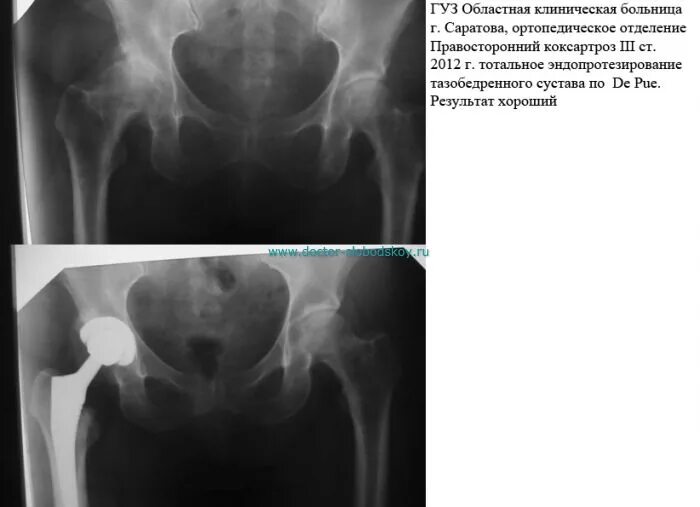

При коксартрозе дают инвалидность